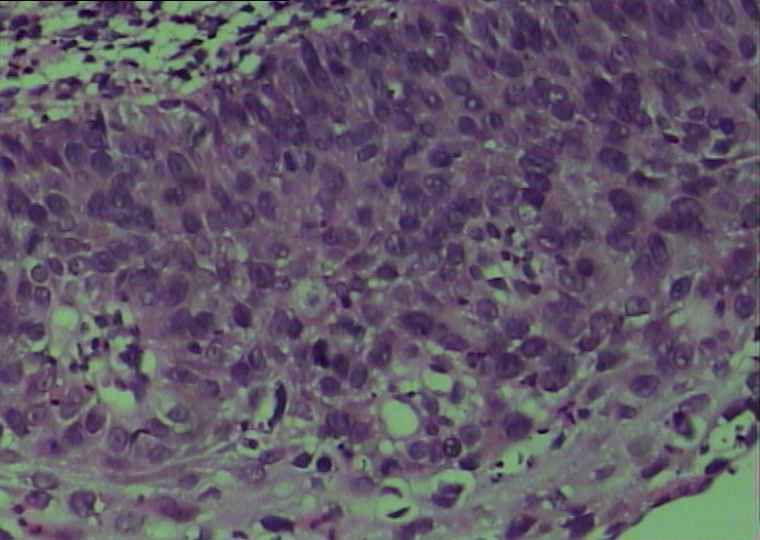

30岁宫颈活检

• 30岁宫颈活检图1

图1

没有人认为是CIN1?宫颈息肉 另外加活检 息肉没传 阴道流血

CINⅡ,累腺

CIN2-3累腺

高度累腺

CIN2,累腺出达CIN3.

为什么会是CIN1呢?首先多形性比较明显,核分裂也易见,也没有明显的分化,这三点都指向高级别的鳞上皮病变啊,至于鉴别可能是修复性改变及不成熟化生,而不是和CIN1鉴别。

CIN级,伴滤泡性宫颈炎。不像累腺

图1 9更倾向与CIN1

图2 4 5 6 更倾向CIN2-3

图3 8那一块不是很肯定是累腺还是切面的问题